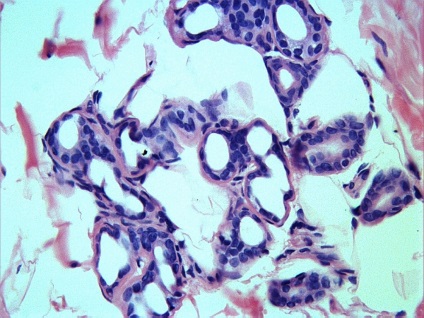

Ma már többféle bőr biopszia, köztük - tűbiopszia, excisional biopszia és derma biopszia. Dermatomális és excíziós bőr-biopszia végre az „akut” vagy „nyitott” módon. Amikor egy szikével biopszia dermatomális felületi réteg a bőr, míg a excisional biopszia - kivágtuk nagyobb bőrterületet, majd varrókészülék (fénykép 1). Ugyanezt a technikát használunk, és ha a biopszia musculocutaneous csapóajtót, ha egyidejűleg kimetszett bőr, a bőr alatti szövet és izom lebeny alá.

Ábra. 6,7,8 érelváltozások a bőr - jelzi biopszia a bőr graft

Ábra. 8.9 10 diák a bőr

Ábra. Immunhisztokémia 11: CD-31 expressziója a vaszkuláris endotéliumon, a bőrben a haemangiomatosis

Következtetés (patológus MD Karev VE): egy jóindulatú daganat tömegének faggyúmirigy; haemangiomatosis bőrben, cutan vasculitis (gyulladásos elváltozások érfalak).